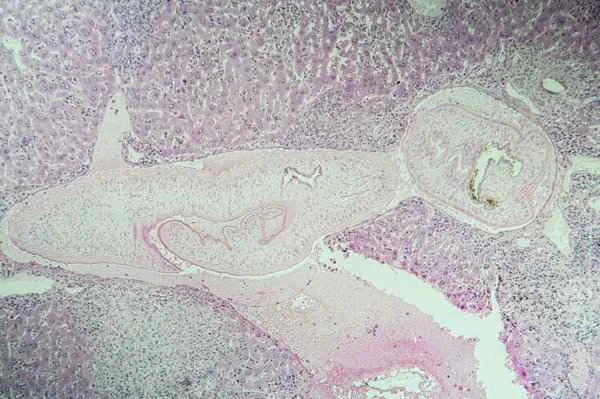

In practice, doctors take a small sample from the scar tissue and examine it under a microscope to observe its cellular structure, arrangement, and whether there is inflammation, fibrosis, or malignant changes. Through these details, doctors can determine the type of scar (such as hypertrophic scars, keloids, etc.) and its potential health risks. This process requires not only meticulous surgical skills but also extensive pathological knowledge to interpret the results.

Examination results typically reveal the health status of scar tissue, such as cell morphology and arrangement, the presence of inflammation, or excessive fibrosis. This information is crucial for determining the nature of the scar and whether further treatment is necessary. It is important to note that while pathological examination results provide vital reference information, their interpretation and application must be combined with clinical symptoms and other examination results. Therefore, an objective and cautious approach should be maintained when using this information to avoid over-interpretation or misdiagnosis.